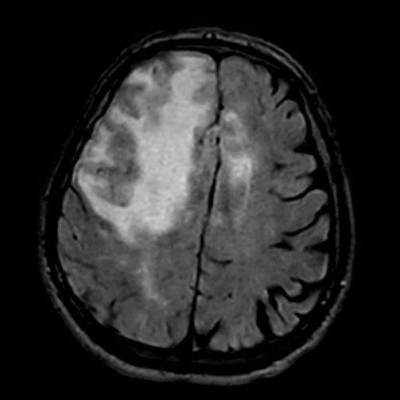

- A) Aksiyel planda FLAIR sekansta asimetrik kortiko-subkortikal vazojenik ödemi düşündüren yüksek sinyalli hafif ekspansil lezyonlar (turuncu ok).

- B) ADC haritasında kolaylaşmış difüzyon (mavi ok).

- Difüzyon kısıtlılığının olmaması, leptomeningeal kontrastlanma, FDG-PET’te düşük aktivite, GRE sekansta yaygın hemosiderin kalıntılarının eşlik etmesi ile karakterizedir.

- 40 yaş üzeri bilinç bozukluğu, davranış değişikliği, fokal nörolojik bulgular, bulguların akut intrakraniyal kanama ile doğrudan ilişkilendirilmemesi, subkortikal beyaz cevhere uzanan asimetrik unifokal ya da multifokal kortiko-subkortikal ödemli lezyonlara serebral mikro/makrokanama, superfisiyal siderozisin eşlik etmesi halinde mutlaka düşünülmelidir.